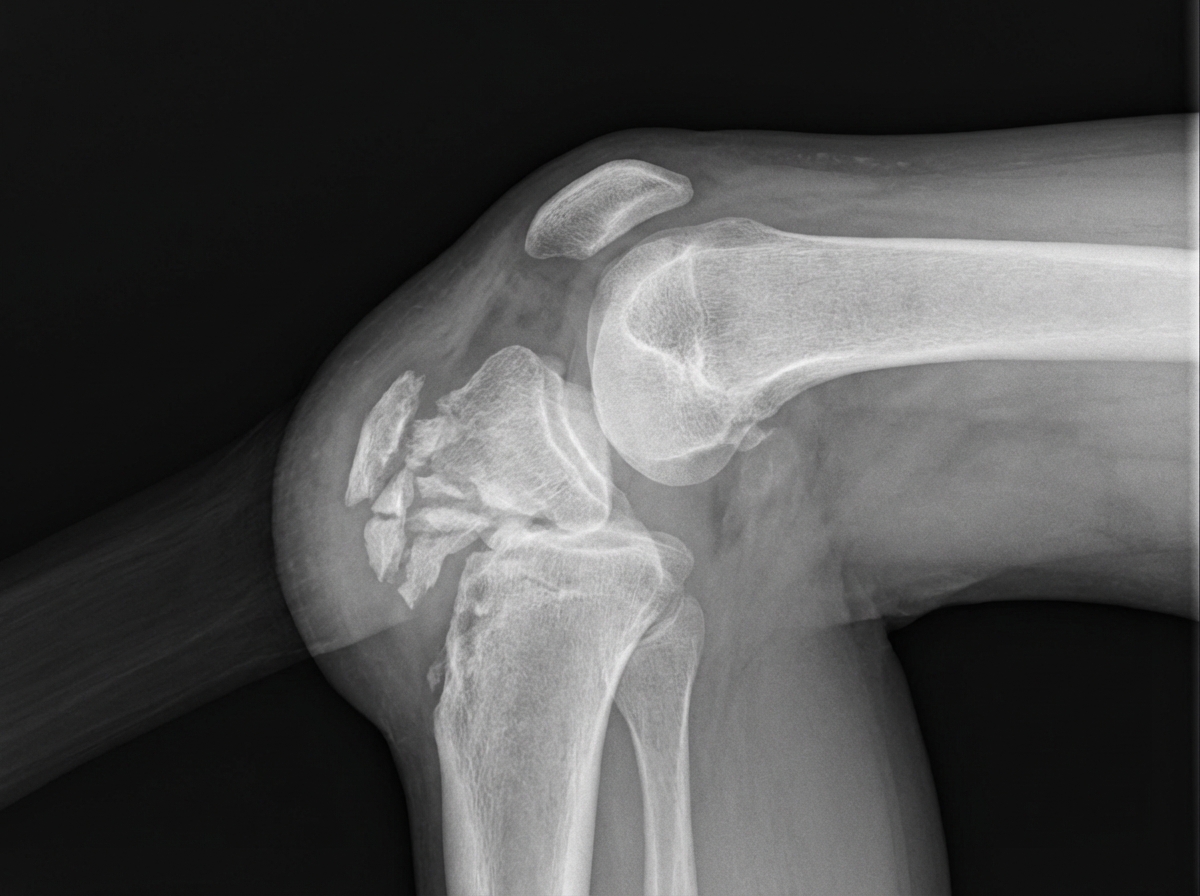

A 12-year-old girl presents to her primary care physician with left knee pain for the past 6 weeks. She recently joined the field hockey team at her school. The pain is the most severe when she is running up and down the stairs at the school stadium. The pain decreases when she goes home and rests after practice. She additionally admits to tripping and landing on her left knee 5 days ago. Physical exam shows a knee with a healing abrasion over the left patella. The tibial tuberosity is tender to palpation. A radiograph of the knee is presented in figure A. Which of the following is the most likely diagnosis?